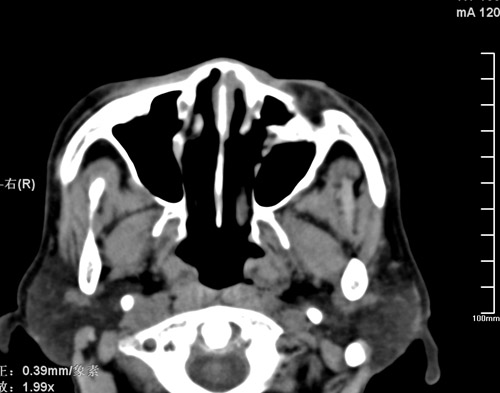

标题: CT17755:女,74 左鼻旁肿胀半年,临床以左上颌窦旁占位行CT [打印本页]

标题: CT17755:女,74 左鼻旁肿胀半年,临床以左上颌窦旁占位行CT

ct考虑鼻前庭囊肿 或鼻翼基底部慢性炎症,左上颌窦少许炎症 请指教

1)考虑左侧鼻前庭囊肿并感染。2)双侧上颌窦炎。

左侧鼻前庭囊肿并感染。双侧上颌窦炎。支持